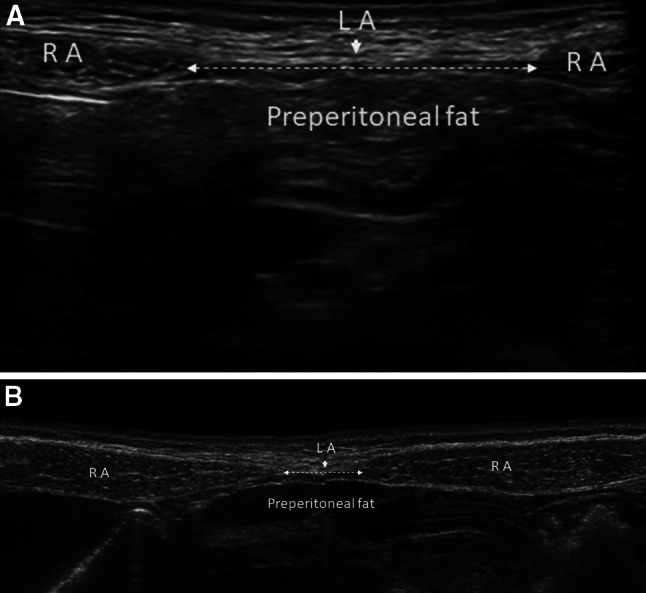

DRAM is characterized by thinning and widening of the linea alba, combined with laxity of the ventral abdominal musculature. This causes the midline to “bulge’’ when intra-abdominal pressure is increased. This clinical condition is often seen in pregnancy [34, 35].

According to the Beer classification, DRAM is defined as an interrectus distance (IRD) of 22 mm or more, assessed three centimeters above the umbilicus. This measure must be taken in a relaxed state of the patient, avoiding traction that can make muscles to get closer to each other. DRAM is frequently misclassified as a primary ventral hernia, although the musculofascial continuity of the midline and the subsequent absence of a true hernia sac is what sets DRAM apart from a ventral hernia [36].

Ultrasound and calipers are satisfactory tools for DRAM measurement. This has been supported by empirical results [43] and further calculations of diagnostic accuracy values based on these results [44].

Ultrasound has been most widely researched with regard to its reliability and has shown to be a reliable method when images were taken by experienced sonographers. Calipers also seem a reliable method for measuring DRAM width (Fig. 8) [45].

Fig. 8.

Diastasis of the rectus abdominis muscles (a, b). Diastasis of the rectus abdominis muscles is defined as an interrectus distance of 22 mm or more (a calipers), assessed three centimeters above the umbilicus. This measure must be taken in a relaxed state of the patient, avoiding traction that can make muscles to get closer to each other. b Ultrasound panoramic image. RA rectus abdominis, LA linea alba